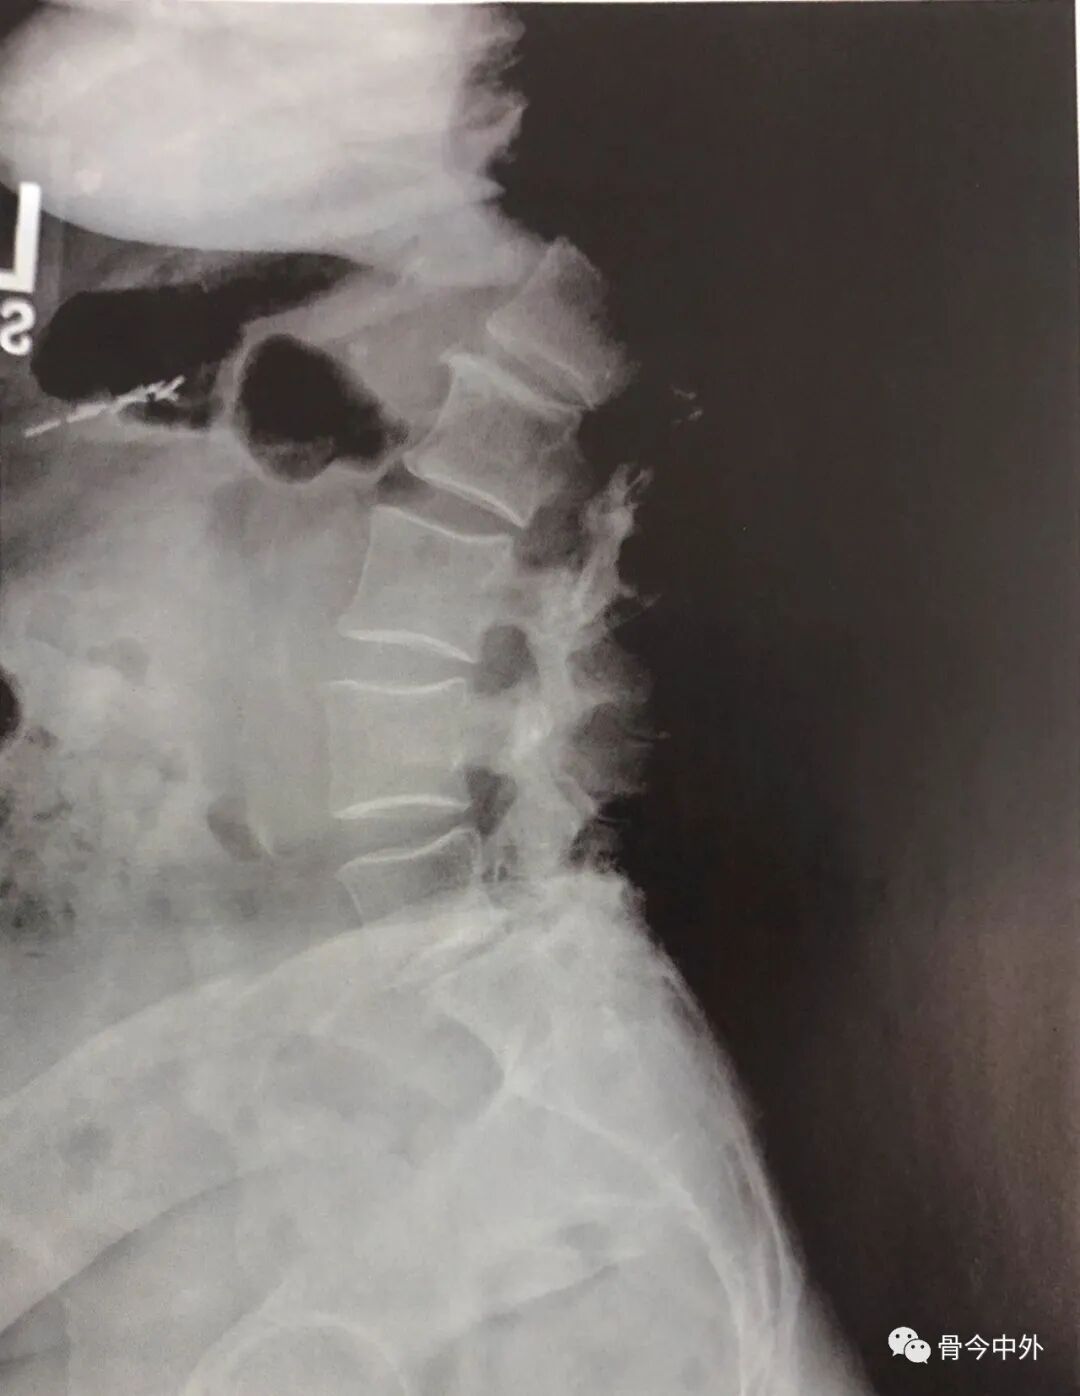

腰椎MRI显示L5椎体Ⅰ度退变性滑脱,伴椎间盘塌陷和椎间孔狭窄(图4)。腰椎动力位X线片显示L5相对S1滑脱为9mm,并在屈曲时加大。